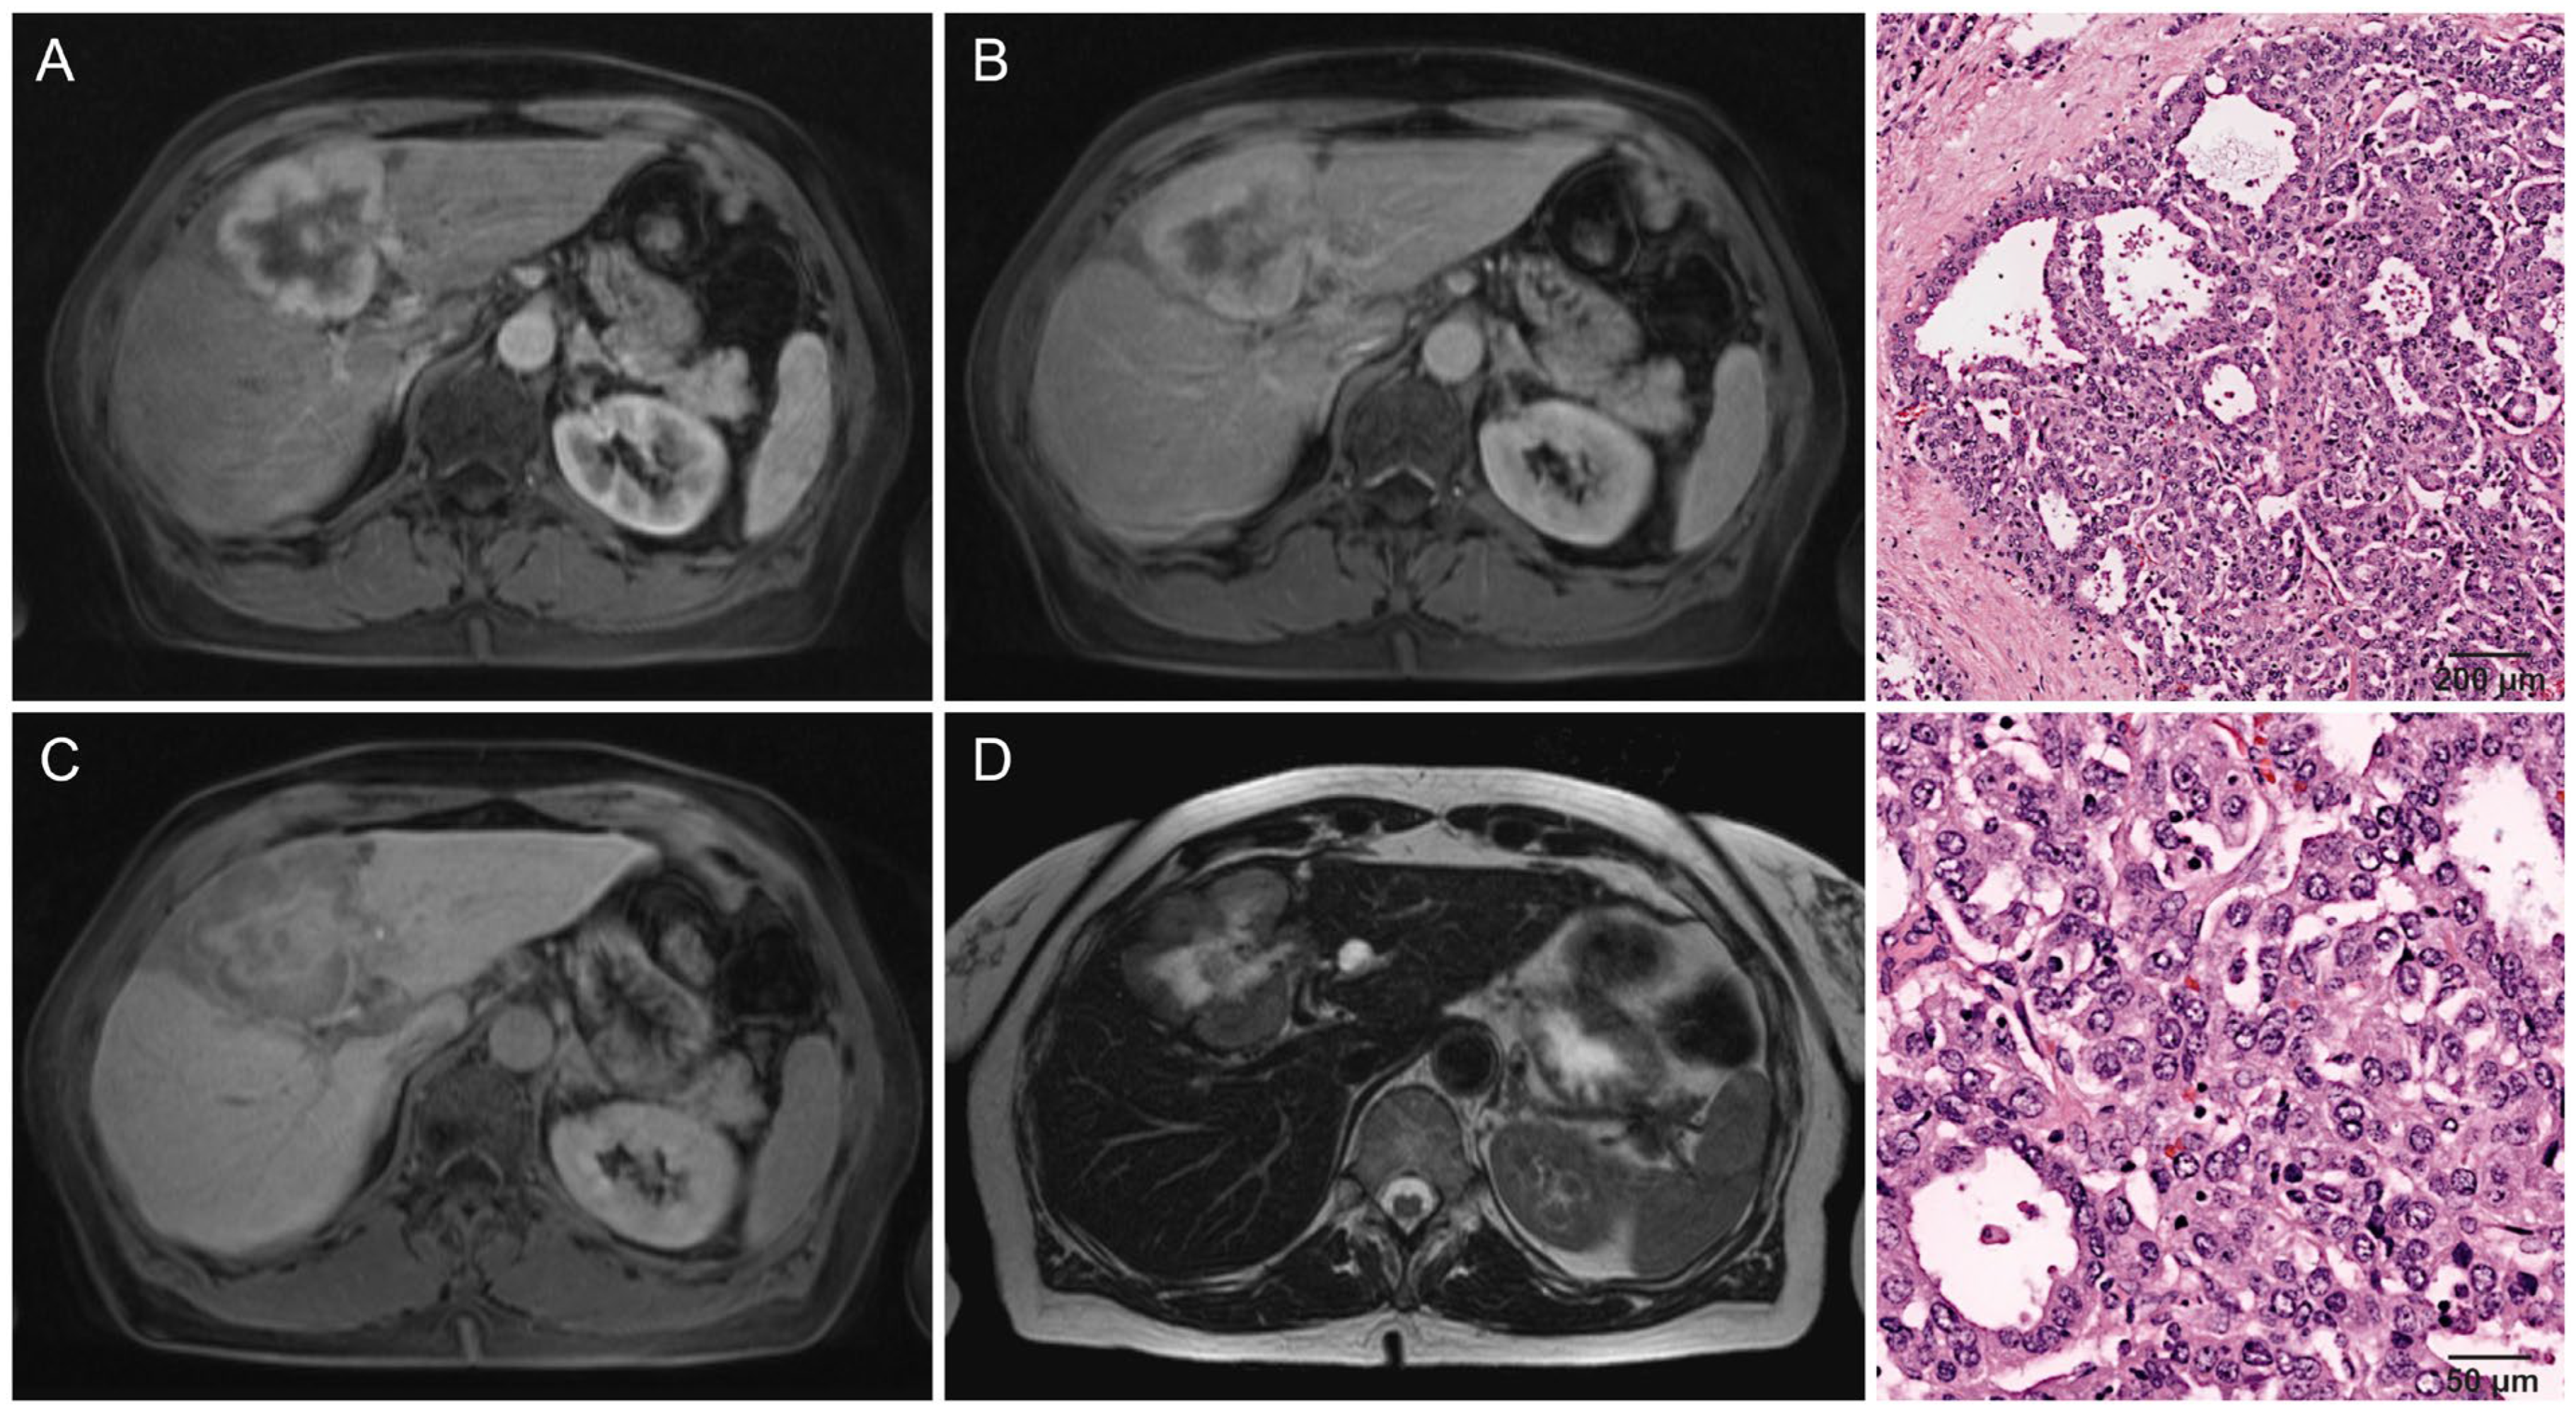

- Kang, Y.; Lee, J.M.; Kim, S.H.; Han, J.K.; Choi, B.I. Intrahepatic mass-forming cholangiocarcinoma: Enhancement patterns on gadoxetic acid-enhanced MR images. Radiology 2012, 264, 751–760. [Google Scholar] [CrossRef] [PubMed]

- Chung, Y.E.; Kim, M.J.; Park, Y.N.; Choi, J.Y.; Pyo, J.Y.; Kim, Y.C.; Cho, H.J.; Kim, K.A.; Choi, S.Y. Varying appearances of cholangiocarcinoma: Radiologic-pathologic correlation. Radiographics 2009, 29, 683–700. [Google Scholar] [CrossRef] [PubMed]

- Min, J.H.; Kim, Y.K.; Choi, S.Y.; Kang, T.W.; Lee, S.J.; Kim, J.M.; Ahn, S.; Cho, H. Intrahepatic Mass-forming Cholangiocarcinoma: Arterial Enhancement Patterns at MRI and Prognosis. Radiology 2019, 290, 691–699. [Google Scholar] [CrossRef] [PubMed]

- Jin, K.P.; Sheng, R.F.; Yang, C.; Zeng, M.S. Combined arterial and delayed enhancement patterns of MRI assist in prognostic prediction for intrahepatic mass-forming cholangiocarcinoma (IMCC). Abdom. Radiol. 2022, 47, 640–650. [Google Scholar] [CrossRef]